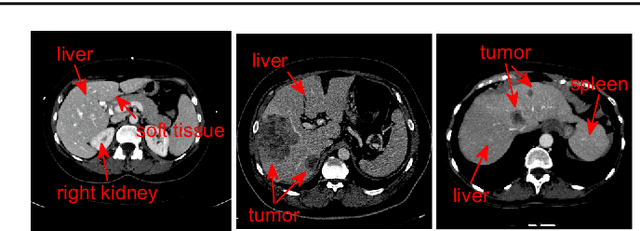

Abstract:Accurate segmentation for medical images is important for clinical diagnosis. Existing automatic segmentation methods are mainly based on fully supervised learning and have an extremely high demand for precise annotations, which are very costly and time-consuming to obtain. To address this problem, we proposed an automatic CT segmentation method based on weakly supervised learning, by which one could train an accurate segmentation model only with weak annotations in the form of bounding boxes. The proposed method is composed of two steps: 1) generating pseudo masks with bounding box annotations by k-means clustering, and 2) iteratively training a 3D U-Net convolutional neural network as a segmentation model. Some data pre-processing methods are used to improve performance. The method was validated on four datasets containing three types of organs with a total of 627 CT volumes. For liver, spleen and kidney segmentation, it achieved an accuracy of 95.19%, 92.11%, and 91.45%, respectively. Experimental results demonstrate that our method is accurate, efficient, and suitable for clinical use.